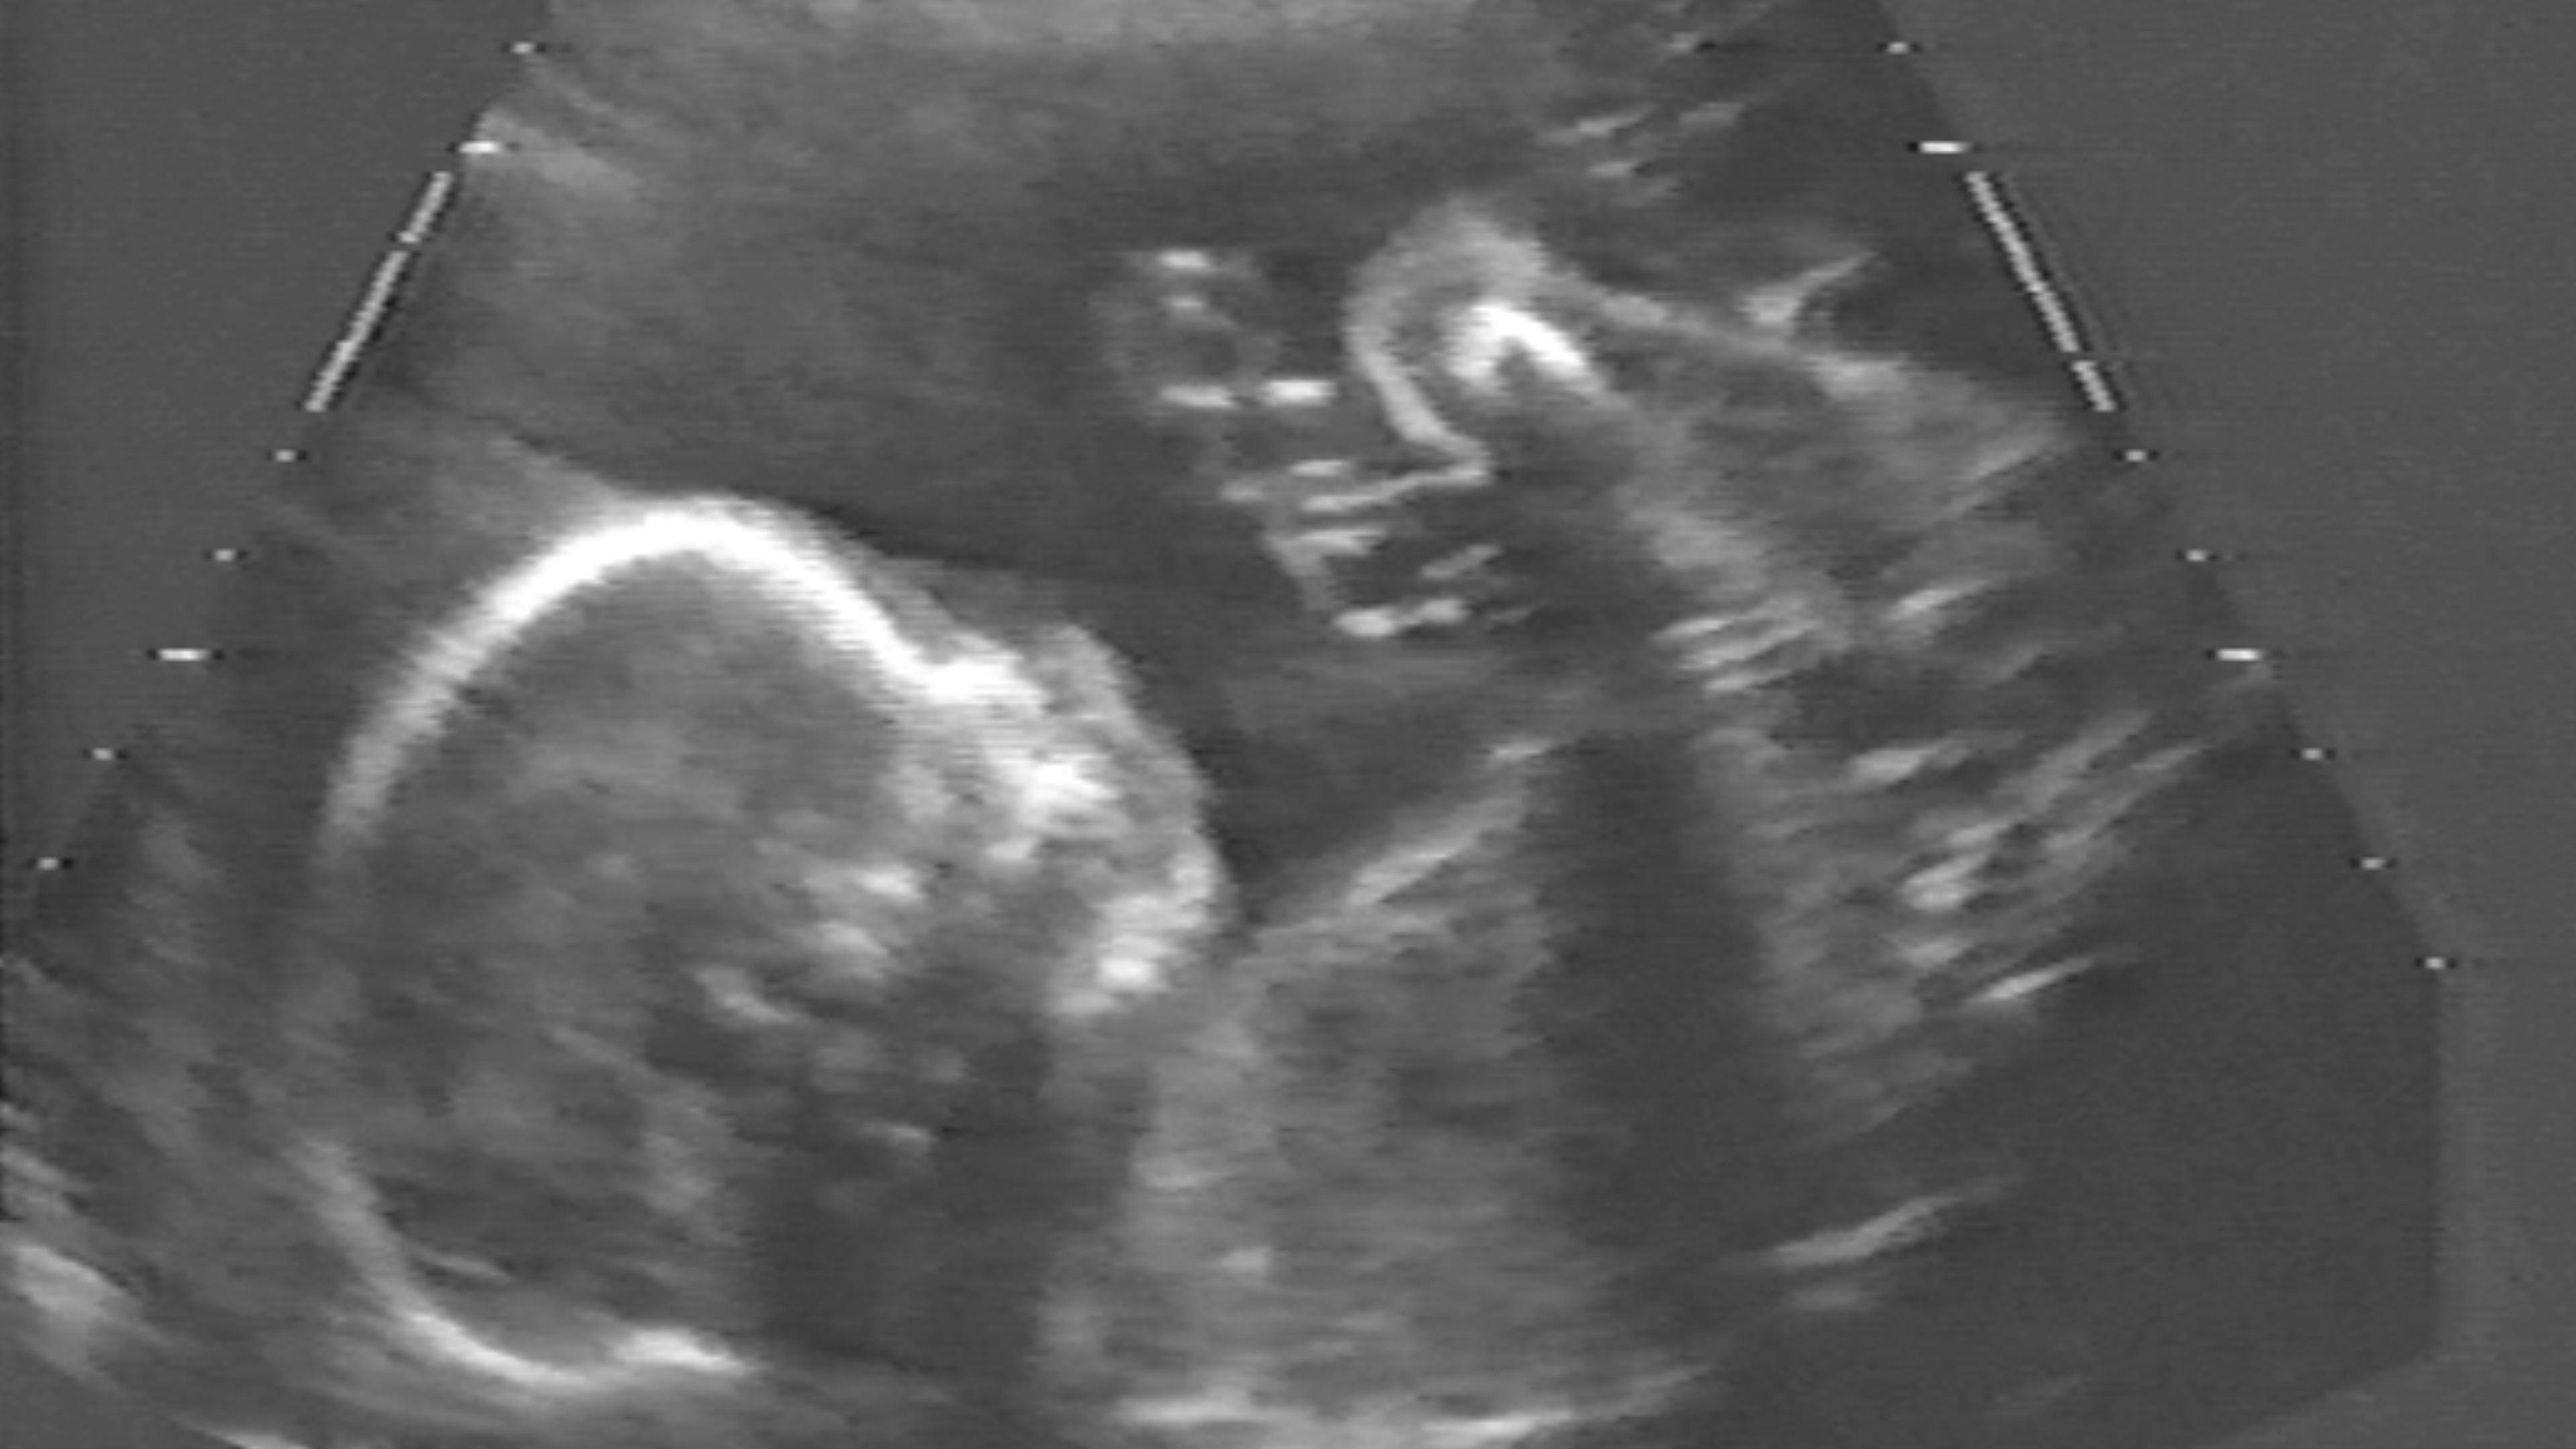

Sonogram of Andrew